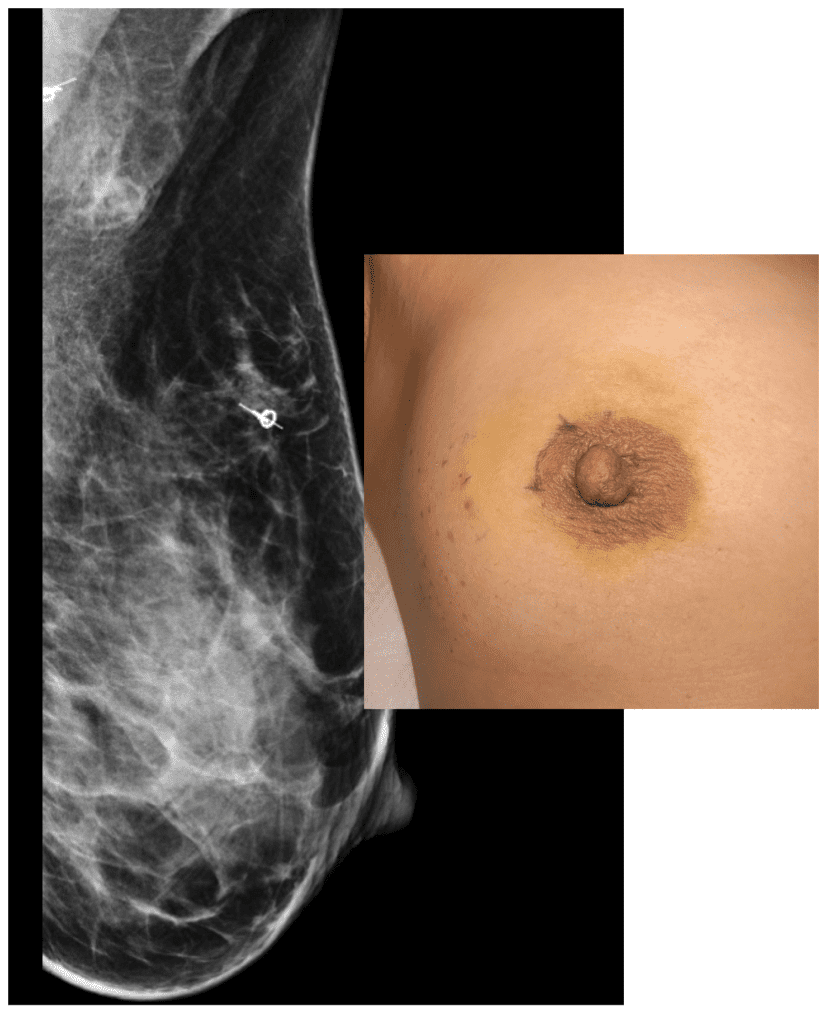

Mammogram showing localization of mass and lymph node for removal as well as skin marking for lumpectomy incision.

Breast conservation lumpectomy 2022

Chemotherapy, left lumpectomy and lymph node biopsy, and radiation

Pregnant patient at 28 weeks who previously had undergone chemotherapy, right breast lumpectomy, and radiation. Her left breast as growing as expected, but the right breast that had undergone radiation was not.